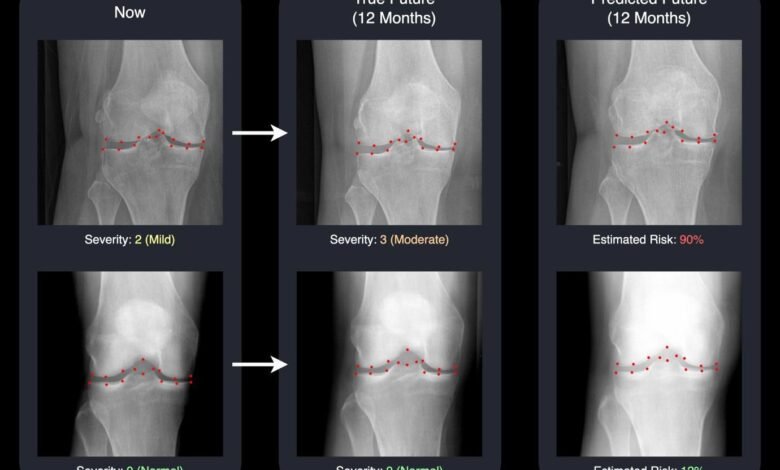

An AI system developed at the University of Surrey can predict future knee X-rays, helping reveal how osteoarthritis may worsen over time. By turning complex predictions into clear images, it gives doctors and patients a better chance to act early.

The findings were presented at the International Conference on Medical Image Computing and Computer Assisted Intervention (MICCAI 2025). The study explains how the Surrey team uses advancedmachine learningto produce a realistic “future” knee X-ray together with a score that estimates how likely the disease is to progress. When viewed together, these results give both doctors and patients a clearer and visual sense of what may lie ahead.

“We’re used to medical AI tools that give a number or a prediction, but not much explanation. Our system not only predicts the likelihood of your knee getting worse – it actually shows you a realistic image of what that future knee could look like. Seeing the two X-rays side by side – one from today and one for next year – is a powerful motivator.

It helps doctors act sooner and gives patients a clearer picture of why sticking to their treatment plan or making lifestyle changes really matters. We think this can be a turning point in how we communicate risk and improve osteoarthritic knee care and other related conditions.”

The system relies on a type of generative AI known as a diffusion model. It creates a projected future knee X-ray and marks 16 key points within the joint. By showing exactly which areas the AI is tracking for change, the system becomes transparent and easier for clinicians to understand and trust.